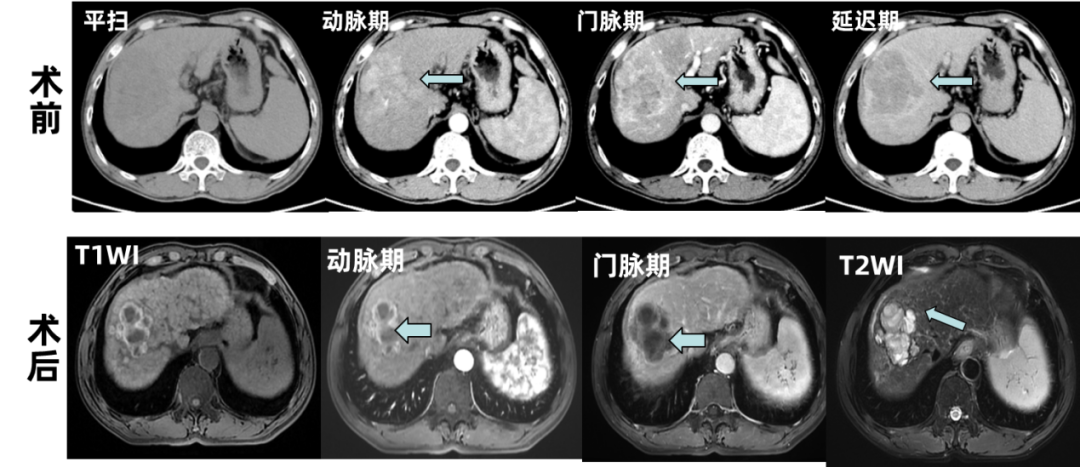

2024-12-13,CT:肝右叶多发肿块、结节,考虑肝癌并多发子灶,肝右、中静脉受累。

图1基线影像学检查

2025-02-15,MR:肝右叶多发肿块、结节,较前缩小、强化减低。疗效评价PR。

图3术前与术后MR检查